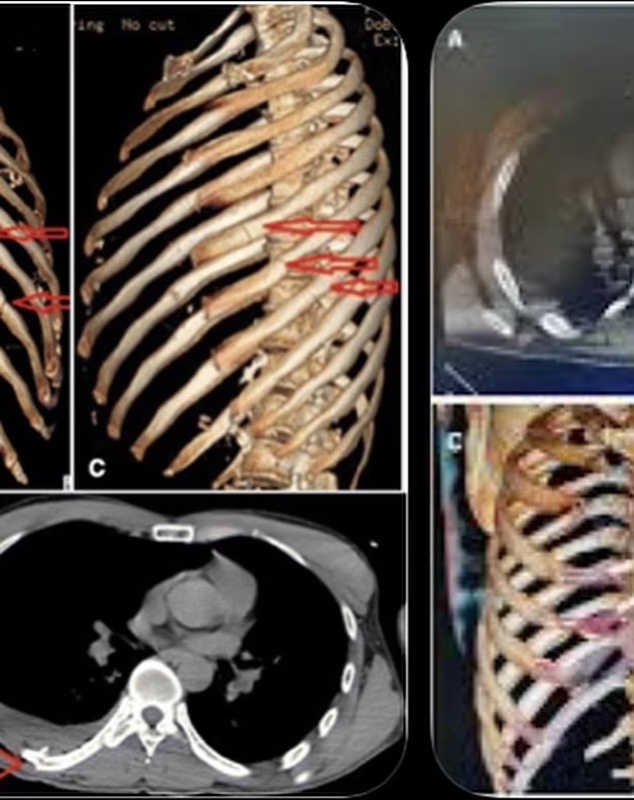

“Pretty messed up but I’m good,” Harrison wrote. “Crash bars are awesome. 3 nights in the hospital. 11 breaks in my rib cage. Will do an episode on @theCoreyHarrisonshow. Sorry Pops looks like I’m missing your wedding.”

The images included medical scans that showed multiple fractures to his rib cage. Harrison did not disclose the location of the crash or additional details surrounding the incident.

Corey shared X-ray scans of his broken bones.